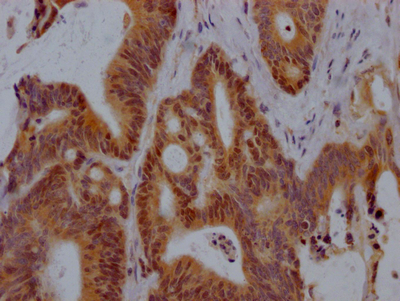

IHC image of CSB-PA006099DA01HU diluted at 1:400 and staining in paraffin-embedded human lung cancer performed on a Leica BondTM system. After dewaxing and hydration, antigen retrieval was mediated by high pressure in a citrate buffer (pH 6.0). Section was blocked with 10% normal goat serum 30min at RT. Then primary antibody (1% BSA) was incubated at 4°C overnight. The primary is detected by a biotinylated secondary antibody and visualized using an HRP conjugated SP system.